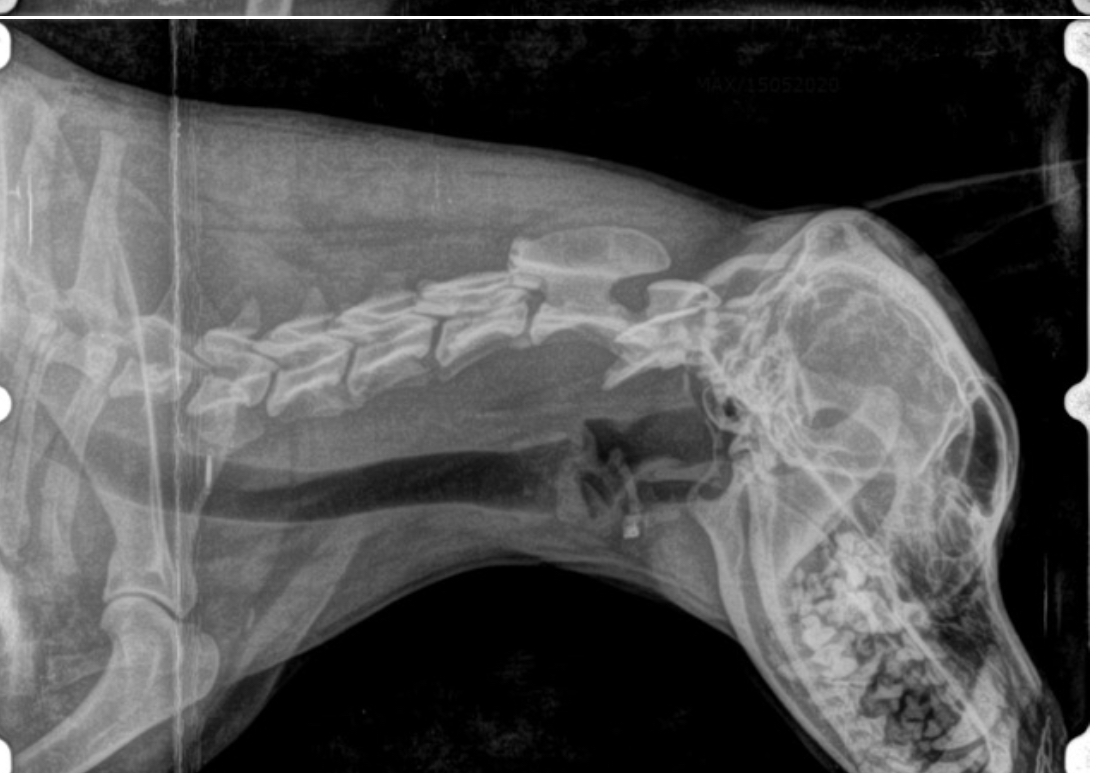

• Estudios Radiológicos

La minuciosa exploración clínica general de nuestras mascotas cuando enferman es vital. Estado de condición corporal, actitid, color de las mucosas, funcionlidad ocular,  frecuencia y calidad cardíaca, frecuencia y calidad respiratoria, estado y tamaño ganglios, palpación profunda de distintas regiones anatómicas para detección de dolor, valorción de funcionlalidad neurológica, auscultación abdominal para valoracación de motilidad instestinal, toma de temperatura por si hubiera fiebre y más aspectos nos llevan a la toma de decisiones ante posibles DIAGNÓSTICOS ante enfermedad que pueda estar ocurriendo. La medicina interna veterinaria es amplia e interesante para velar por el bienestar y salud de las mascotas. Los diferentes grados de gravedad varían y por ende sus tratamientos que pueden ser conservadores o quirúrgicos. La experiencia de los años y la buen disposición avala el servicio.